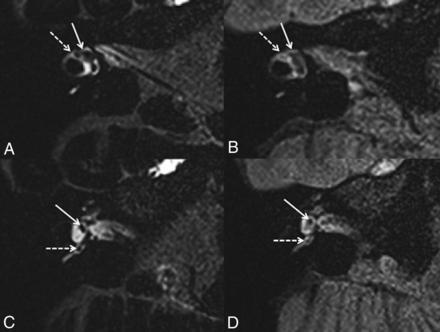

With hVFA sequences (Fig 3), EH was observed in 13/32 ears (40.6%) according to reader A (10/19 symptomatic and 3/13 asymptomatic ears) and 10/32 ears (31.3%) according to reader B (7/19 symptomatic and 3/13 asymptomatic ears). The Cohen κ coefficient was 0.26. There was no significant association between the clinical symptomatology and the presence of EH (P = .15, OR = 3.55; 95% CI, 0.63–26.62; and P = .47, OR = 1.90; 95% CI, 0.32–14.47, according to readers A and B respectively).

A 42-year-old woman with right possible MD. Right axial CFA (A) and hVFA (B) sequences through the inferior part of the vestibule show a normal saccule (white arrow) and posterior ampulla (white dotted arrow) in both sequences. A 43-year-old man with a right definite MD. Right axial CFA (C) and hVFA (D) sequences through the inferior part of the vestibule show saccular hydrops (white arrow) in both sequences. A 35-year-old woman with a right possible MD. Right axial CFA (E) and hVFA (F) sequences through the inferior part of the vestibule and the posterior ampulla (white dotted arrow). With the CFA sequence, the right saccule appears normal (white arrow). With the hVFA sequence, reader A described a right saccular hydrops, while reader B defined the right saccule as normal. The saccule (white arrow) and the posterior and lower parts of the utricle (white arrowhead) were confluent without expansion of these 2 structures.

With CFA sequences (Fig 3), both readers reported EH in 14/32 ears (43.7%: 12/19 symptomatic and 2/13 asymptomatic ears). The Cohen κ coefficient was 1. We found a significant association between the clinical symptomatology and the presence of EH (P = .01, OR = 8.73; 95% CI, 1.33 − 103.73).